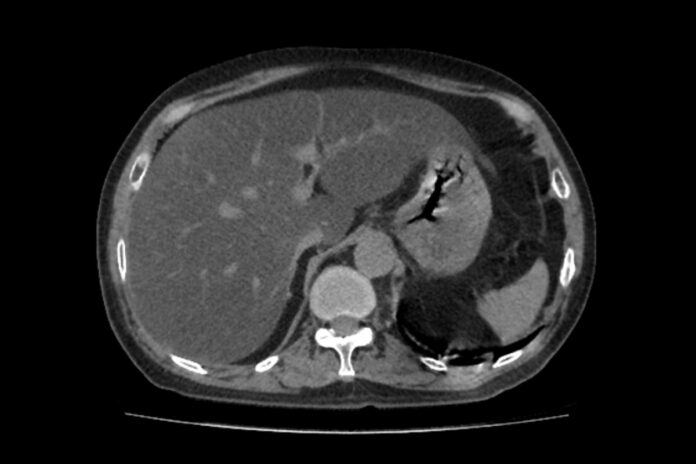

A condição de gordura no fígado afeta em torno de 30% da população brasileira